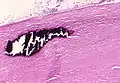

Extensive fibrosis of pleura and lung parenchyma.

The arrow points to an uncoated segment of asbestos fiber in this ferruginous body.